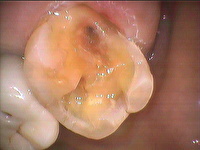

①左上の奥歯の銀歯の横が欠けてきました ②外してみると内部で虫歯です ③虫歯を取って型取りをしました ④アレルギーが無く丈夫なジルコニア製のかぶせ物を接着しました。違和感もなく大変喜ばれています。費用は7.5万円+税位です。

治療前後の写真